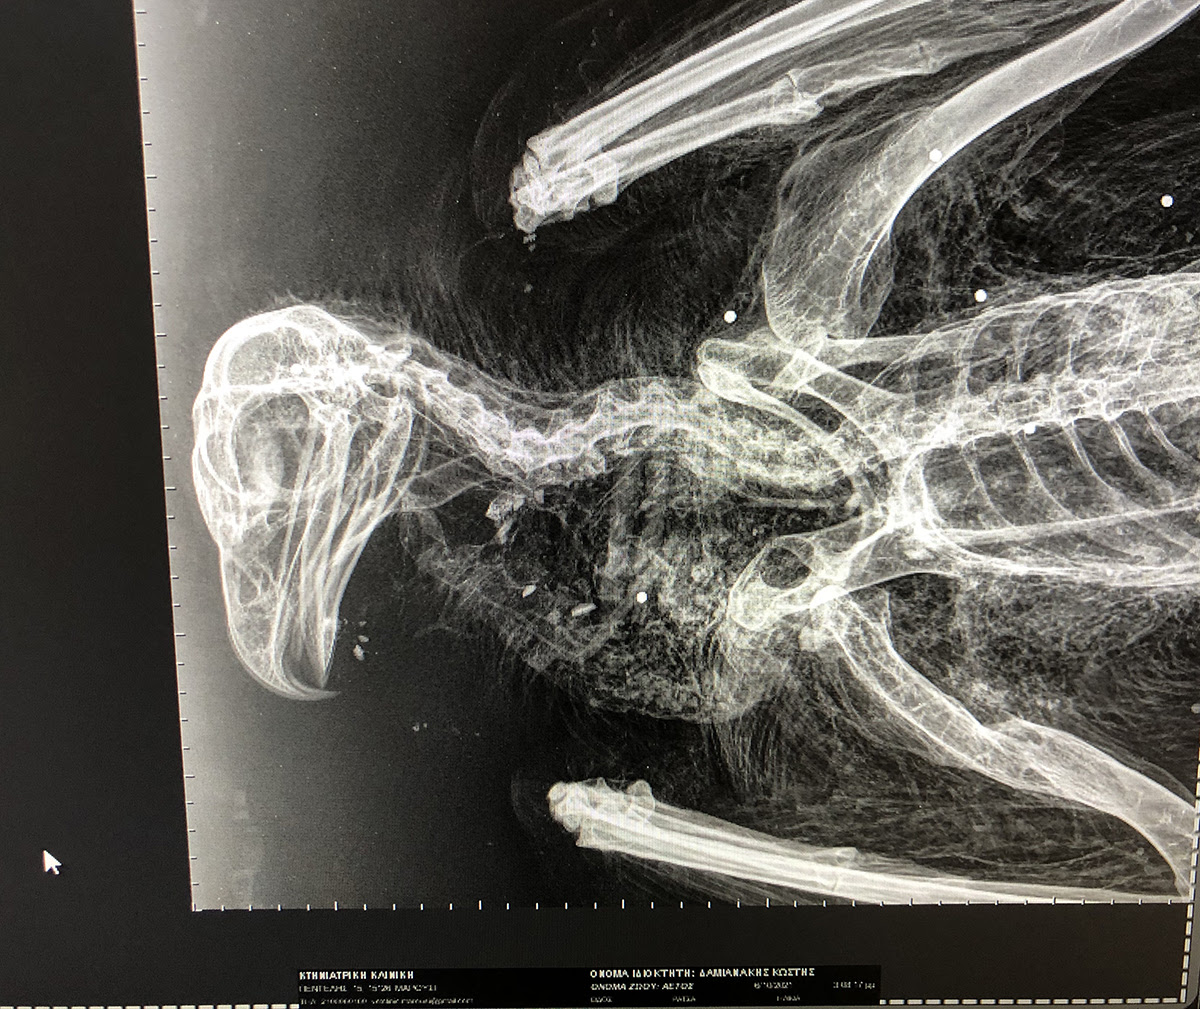

Στις 6 Οκτωβρίου 2021, μέλος της Ομάδας του Προγράμματος LIFE Bonelli eastMed για την προστασία του Σπιζαετού περισυνέλλεξε νεκρό νεαρό Χρυσαετό μεταξύ Καπετανιανών και Λούκιας στον Δήμο Γόρτυνας. Ο προστατευόμενος αετός είχε γεννηθεί σε φωλιά στα Ανατολικά Αστερούσια Όρη πριν από περίπου ενάμιση χρόνο και είχε σημανθεί με δορυφορικό πομπό για την επιστημονική παρακολούθηση των μετακινήσεών του. Ο νεαρός Χρυσαετός υποβλήθηκε σε ακτινογραφίες και νεκροψία στην Κτηνιατρική Υπηρεσία Ηρακλείου όπου διαπιστώθηκε ότι πυροβολήθηκε στον αέρα από σχετικά κοντινή απόσταση.